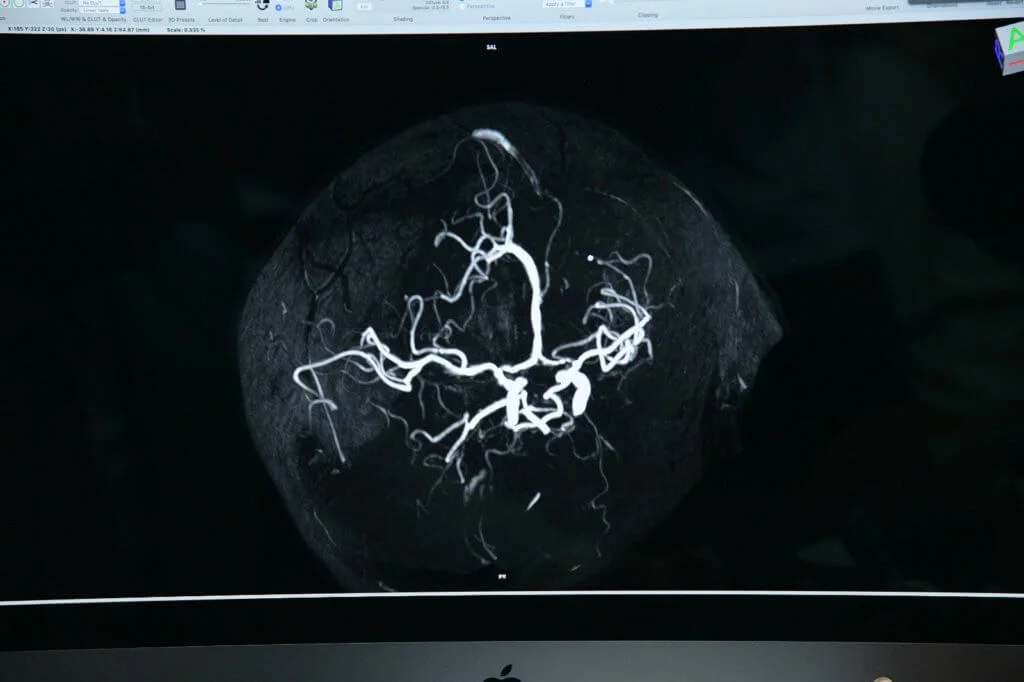

現在我們可以透過儀器,不用開胸破膛,就能監測到血管的流通量,了解血管有沒有收窄及內壁的情況,可以進行預防性處理,血管壁狹窄或有血管瘤,這些都是造成中風的因素,預早察覺就有相對可靠的方法作出處理和預防。

血管壁狹窄或有血管瘤,都是造成中風的因素。